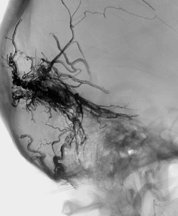

Durale AV Fisteln sind Kurzschlußverbindungen zwischen einer Arterie und einer Vene auf Ebene der harten Hirnhaut (Dura). Sie können nach einer Schädelverletzung oder eine Thrombose eines venösen Blutleiter im Gehirn entstehen, aber oft kann die Ursache nicht sicher bestimmt werden. Bei AV-Fisteln strömt arterielles Blut ohne das zwischengeschaltete Kapillarbett direkt in venöse Gefäße. Aufgrund des höheren Drucks kommt es zu einer Aufweitung der Venen, wodurch das Risiko einer Hirnblutung zunimmt.

Ist eine AV-Fistel durch MRT und eine diagnostische Angiographie sicher nachgewiesen, gibt es in Abhängigkeit von der Lage und Ausdehnung der Fistel verschiedene endovaskuläre Behandlungsoptionen. Heute wird in den meisten Fällen versucht, die AV-Fistel unter Erhalt der venösen Blutleiter zu veröden (Embolisation). Hierfür wird ein sehr dünner Katheter („Mikrokatheter“) über die Leiste bis in die Fistelgefäße geführt. Dies geschieht unter Vollnarkose. Über den Katheter wird ein Embolisat in die Fistelgefäße gespritzt, um diese zu verkleben bzw. zu verstopfen. Für die Embolisation kommen verschiedene Materialien zur Anwendung, überlicherweise werden heute Flüssigembolisate verwendet. Bei ausgedehnten Fisteln kann ein Ballonkatheter über die Leistenvene in den beteiligten venösen Blutleiter in das Gehirn eingelegt werden, um die Vene während der Embolisation vor einer Verstopfung durch das Flüssigembolisat zu schützen. Je nach Größe und Lokalisation der Fistel sind mitunter mehrere Behandlungen notwendig.